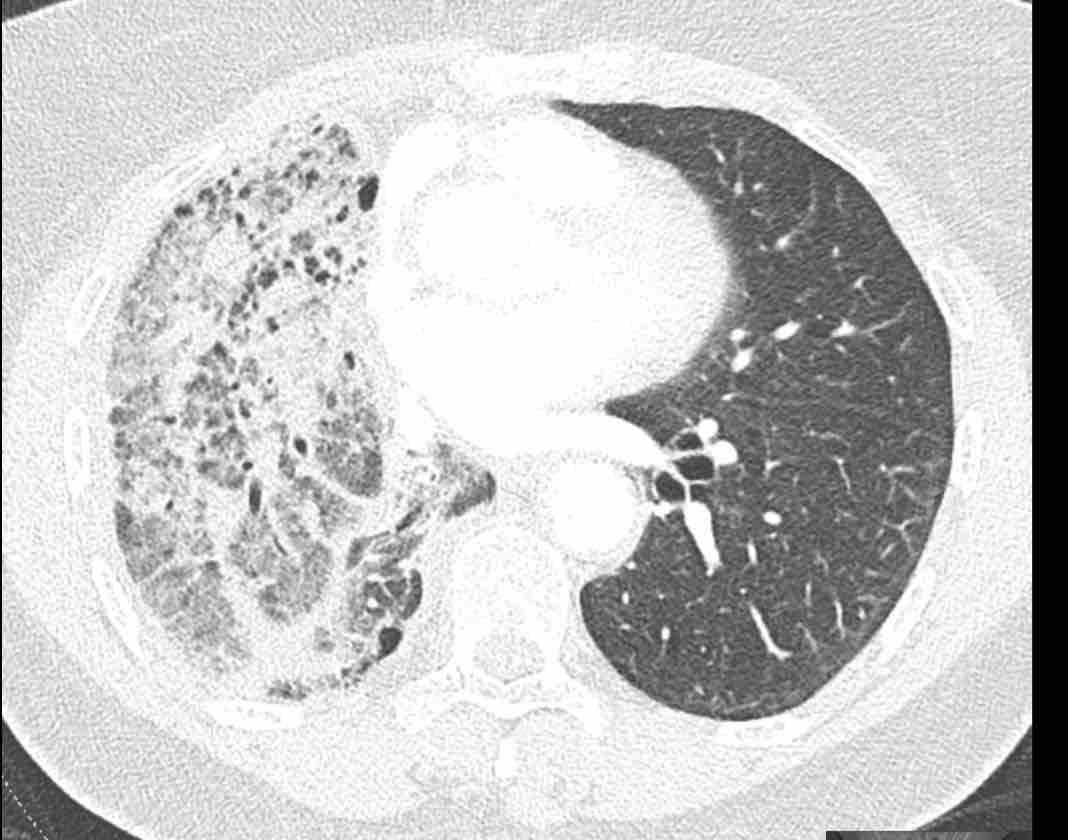

Các hình ảnh này của một bệnh nhân nữ 65 tuổi sau khi đã cắt thùy trên phổi phải trước đó.

Trước tiên, hãy cuộn qua các hình ảnh.

Hình ảnh

Theo dõi lần lượt các phế quản giúp xác định mỏm cắt thùy trên phổi phải (RUL), phế quản thùy giữa bị tắc nghẽn và các phế quản thùy dưới còn thông.

Điều này xác định mô phổi bị di lệch xuống dưới chính là thùy giữa phổi phải (RML), thấy rõ nhất trên mặt phẳng đứng dọc.

Thùy giữa phổi phải bị phù nề và không còn được tưới máu.

Ngoài ra còn thấy hình ảnh ứ máu và xẹp phổi ở các phân thùy đáy của thùy dưới phổi phải (RLL), hiện nằm phía trên thùy giữa phổi phải đã bị nhồi máu.